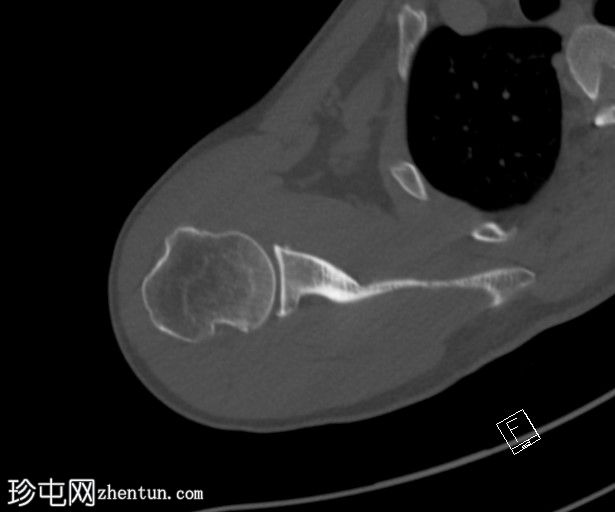

CT

轴位

非增强

CT显示肱骨头后外侧缘存在缺损及骨碎片,提示Hill-Sachs损伤。

右侧肩胛盂前下缘可见一小块骨碎片,提示Bankart损伤。